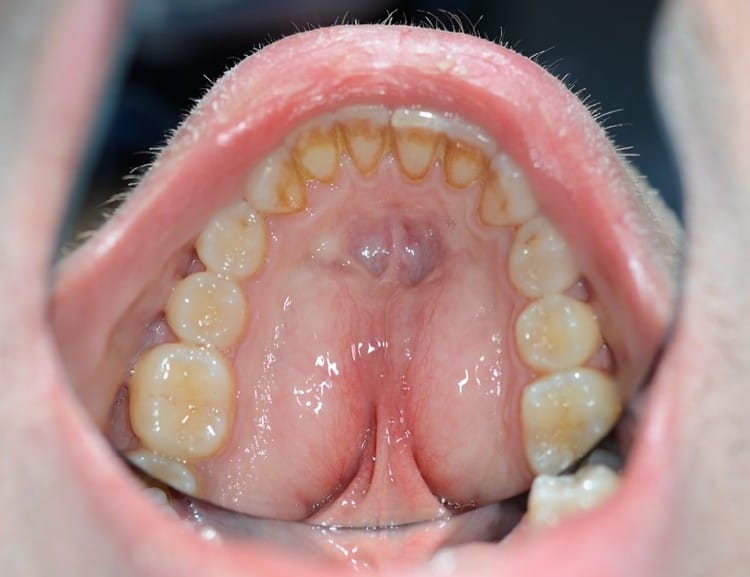

- Torus palatinus (bild 2)

Torus palatinus

Torus palatinus är en benig utväxt av varierande storlek och form oftast belägen centralt i hårda gommen. Patienter kan uppleva besvär i form av sår och trauma vid födointag, svårigheter med tal.